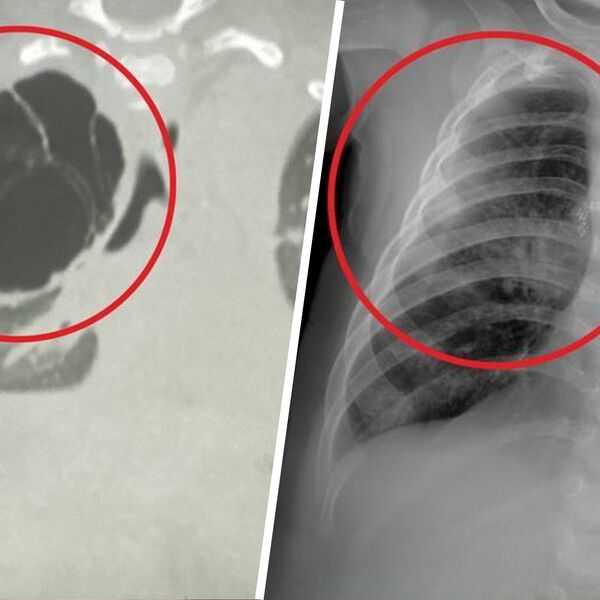

Как рассказали медики, образование было обнаружено во время воспалительного процесса, вызванного острой респираторной вирусной инфекцией. Киста занимала большую часть правого легкого ребенка и не давала ему полноценно развиваться. Врачи приняли решение удалить образование.

«Детские хирурги провели торакоскопическую операцию: без разреза аккуратно удалили кисту вместе с пораженной частью верхней доли правого легкого», — поделились в минздраве.

Операция длилась около часа и завершилась благополучно. Размер кисты составил около 15 сантиметров.